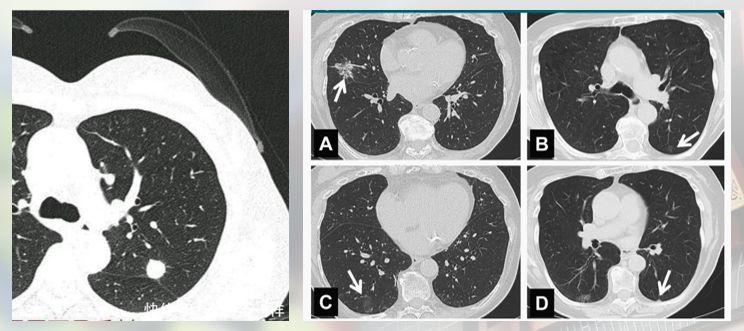

结节有孤立性肺结节和多发性肺结节两种,顾名思义,多发性肺结节一般为一叶肺或者双侧肺上有多个结节,甚至肺结节的数量多至布满整个肺。唐小军教授谈到,这些情况都将影响着治疗方式的选择,手术的考虑等。

肺结节的分布和个数

唐教授还提到一种需观察后再进行手术的情况,即双肺多发性磨玻璃结节,由于需切除的结节过多,要先由医生判断哪些是危险结节,有选择地进行切除。